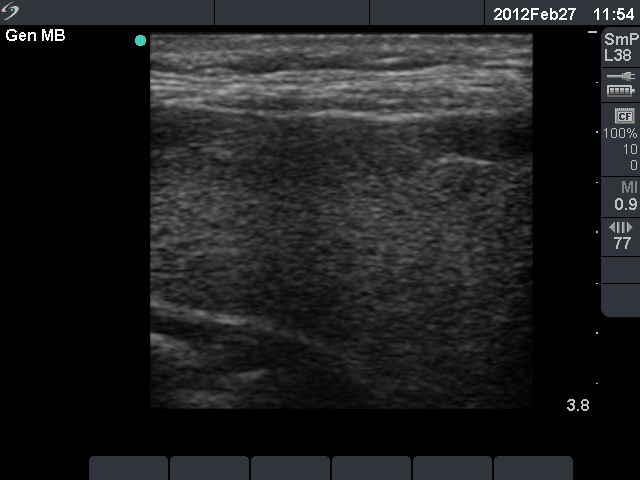

Subacute granulomatous de Quervain's thyroiditis - Case 15. (ultrasonographic picture 2)

Right lobe, longitudinal scan. There are several moderately hypoechogenic areas with indistinct borders.